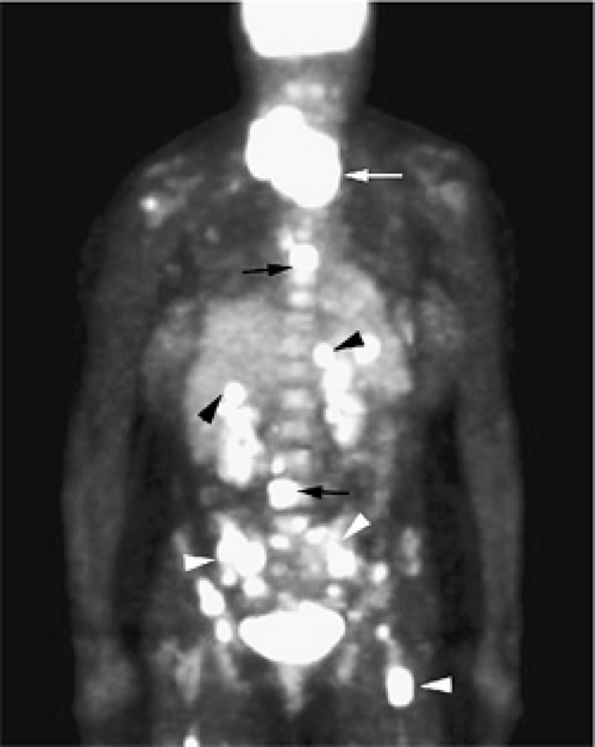

FIGURE 13.33 ● Whole-body FDG-PET scan in a patient with lymphoblastic lymphoma. Large mass with abnormal FDG uptake is noted involving the upper mediastinum (white arrow). Increased uptake is noted throughout the spine (black arrows), the pelvis, and the proximal femurs (white arrowheads). Foci of increased uptake in the liver are consistent with tumor involvement (black arrowheads).

|